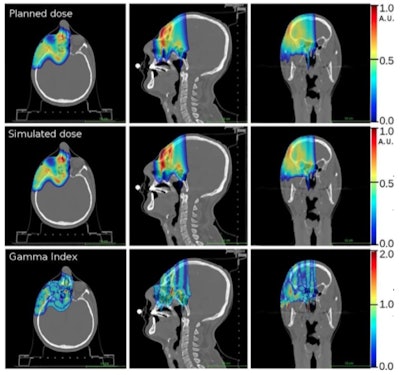

Dose distribution measured by the INSIDE system versus the Monte Carlo simulation. The production of positron emitters increases over the course of the fraction and activity in the beam direction expands due to an increase in proton energy characteristic of the CNAO beam line over time. (Courtesy: E Fiorina et al, Physica Medica, 10.1016/j.ejmp.2018.05.002 © 2018, Associazione Italiana di Fisica Medica)

In a comparison with the prescribed treatment plan, dose distributions derived from the simulation proved accurate. Gamma tests demonstrated 91% of voxels agreed to within 3% or 3 mm and 98% of voxels to within 5% or 5 mm.

Particle range in the predicted and measured PET images was quantified using iso-activity surfaces corresponding to 10% of the maximum voxel intensity in the scans. The researchers demonstrated that the average distance between the surfaces in the two images was less than 1 mm. The analysis was carried out offline, but the authors envisage that a real-time implementation will be straightforward, enabling a quantitative analysis while the patient is still being irradiated.